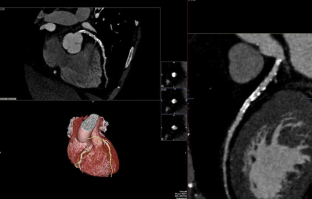

Fig. 2